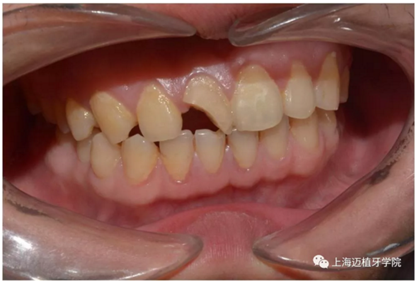

術(shù)前照片

主訴:前門外傷牙根折要求修復?現(xiàn)病史:前門牙外傷,劈裂至根部,無法固定及其他修復,要求種植?檢查:11牙冠2/3缺損,唇腭向劈裂,唇部紅腫。 CT示根折, 骨寬度9.47mm,距鼻底12.34mm,Ⅲ類骨。 口腔衛(wèi)生一般